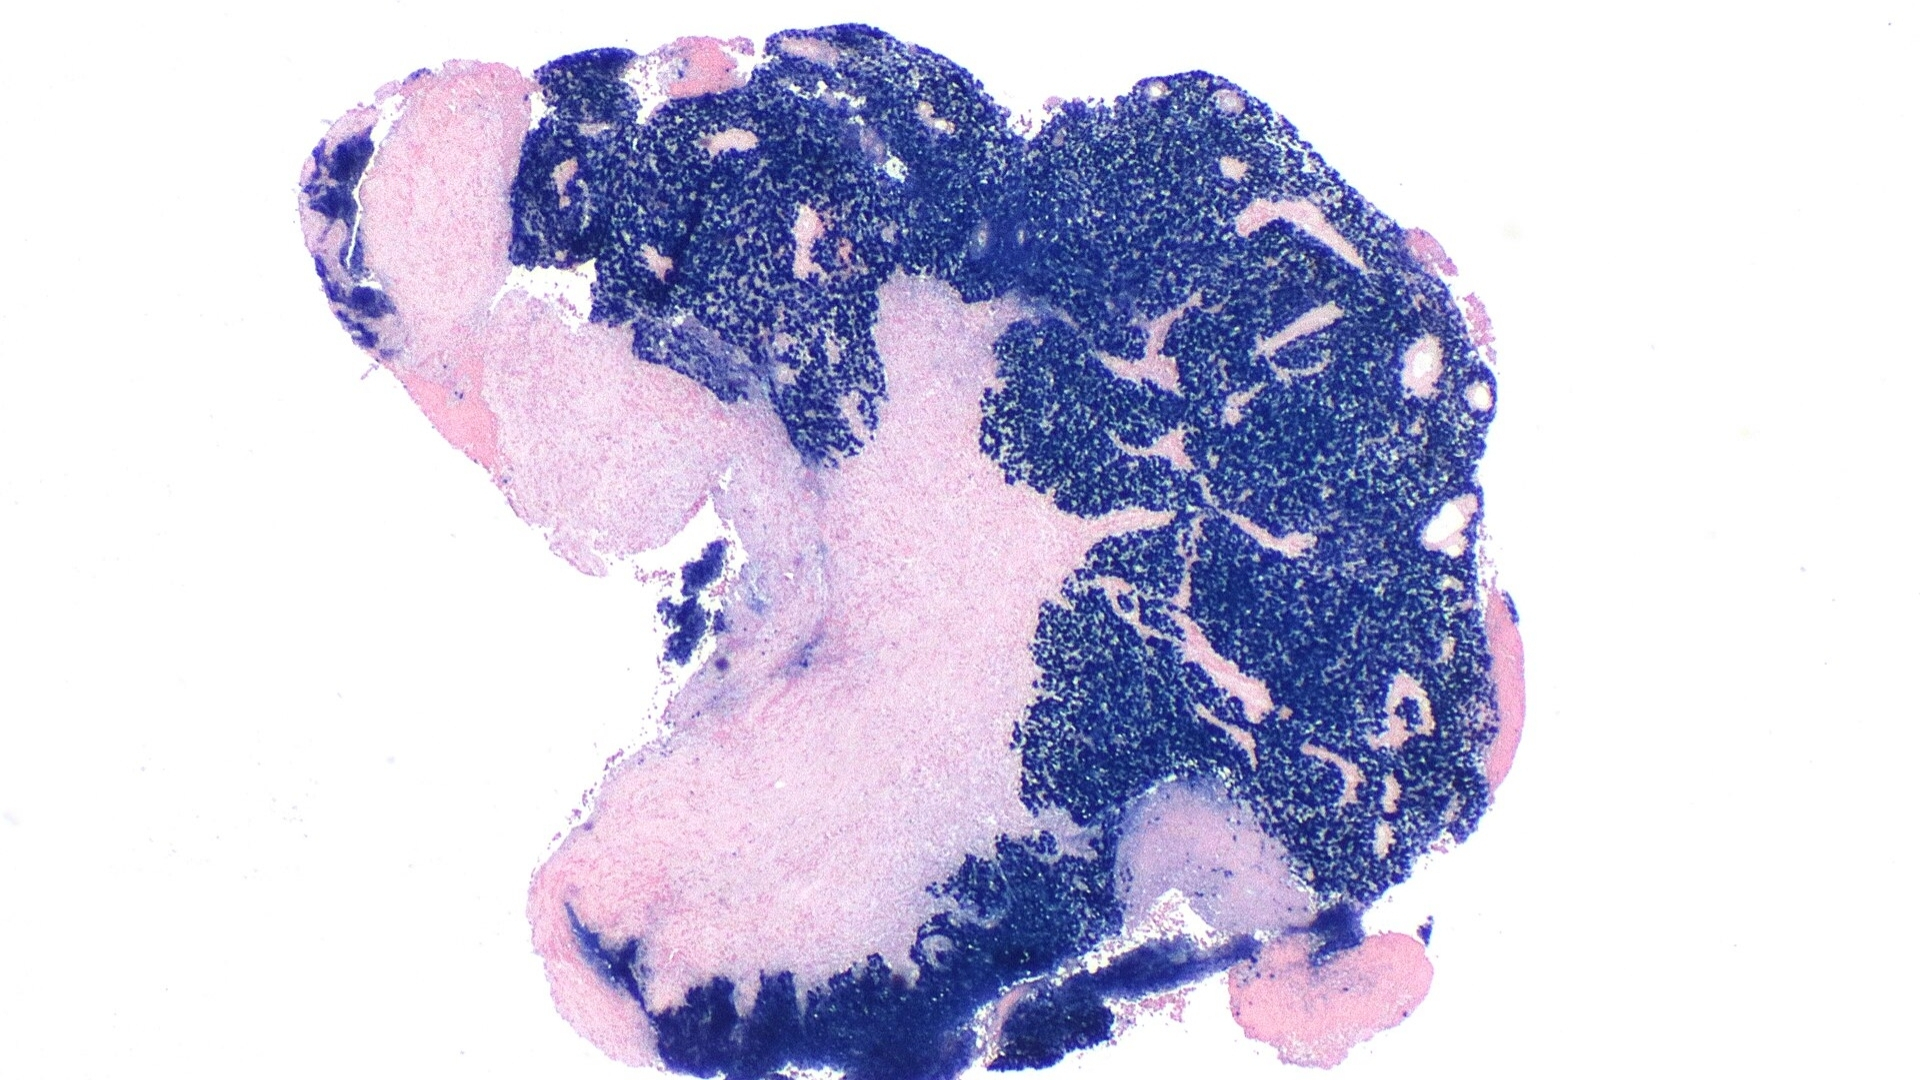

了解鼻咽癌 (Nasopharyngeal Carcinoma) 需要深入瞭解其生物機制。從細胞層面來看,鼻咽癌起源於鼻咽上皮細胞的惡性轉變和不受控制的增生。在癌症中,鼻咽癌與 Epstein-Barr 病毒 (EBV) 感染有極高的關聯性,對於腫瘤的發展和惡性潛力有顯著的影響。

• 鼻咽癌 (Nasopharyngeal Carcinoma) 涉及快速且異常的細胞增生,通常是透過 EBV 感染途徑的病毒基因干擾所促成。

• 與 Epstein-Barr Virus (EBV) 感染的強烈關係持續存在,在亞洲鼻咽癌族群的活檢分析中幾乎普遍。